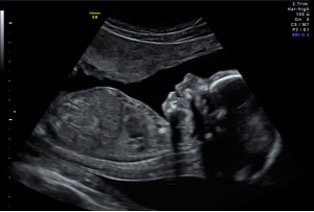

2./3. Trimester (20.-22. SSW)

Auch weiterführende Sonographie, Feinultraschall, Organdiagnostik oder Fehlbildungsultraschall genannt. Mit diesen Ultraschalluntersuchungen können viele kindliche Entwicklungsstörungen und Organfehlbildungen erkannt werden Die Aussagekraft von Ultraschalluntersuchungen hängt auch immer vom Schwangerschaftsalter, der Lage des Kindes, Plazenta, Fruchtwassermenge, Dicke der mütterlichen Bauchdecke und vielem mehr ab. Auch nutzen wir die Möglichkeiten der 3D/4D-Sonographie.

Bei vielen angeborenen Krankheiten wie zum Beispiel Herzfehlern, Spina bifida („offener Rücken“), Zwerchfelldefekten und dem Zwillingstransfusionssyndrom, aber v. a. auch bei Wachstumsstörungen ist die kindliche Prognose bei rechtzeitiger Erkennung und Behandlung bereits vor oder direkt nach der Geburt besser. Wichtig zu wissen ist auch, dass nicht alle angeborenen Krankheiten vorgeburtlich erfasst werden können und nicht alle Erkrankungen zu jedem Zeitpunkt entdeckt werden können. Studien zeigen eine Erkennung von 80-90 % der schweren Fehlbildungen.